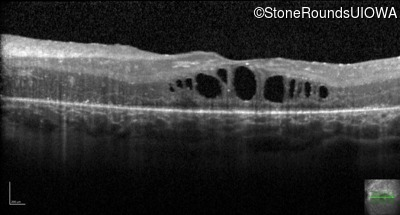

Age at visit: 17 years

This 17 year old female feels that the vision in her right eye has worsened since her cataract surgery 8 weeks ago.

Age at visit: 5 years

Age at visit: 7 years

Age at visit: 9 years

Age at visit: 11 years

Age at visit: 18 years